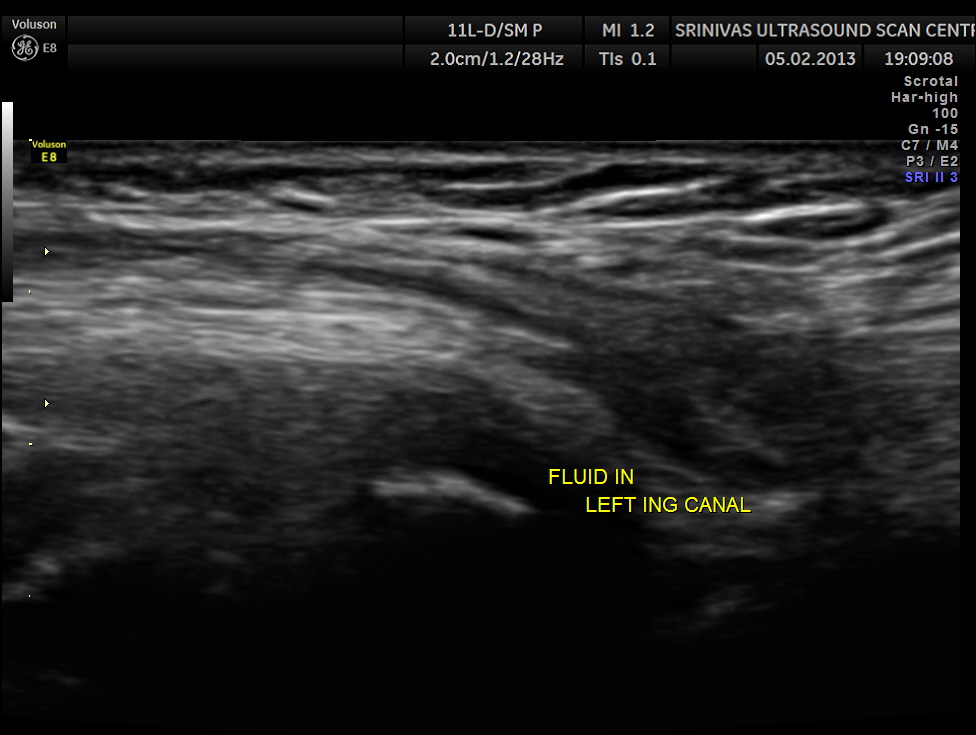

This was a 11 year old boy referred for evaluation of left inguinal swelling on and off.

The clinical diagnosis was bubunocele.

(medicine) An inguinal hernia, especially of the incomplete variety in which the hernial pouch descends only as far as the groin, forming a swelling there like a bubo.